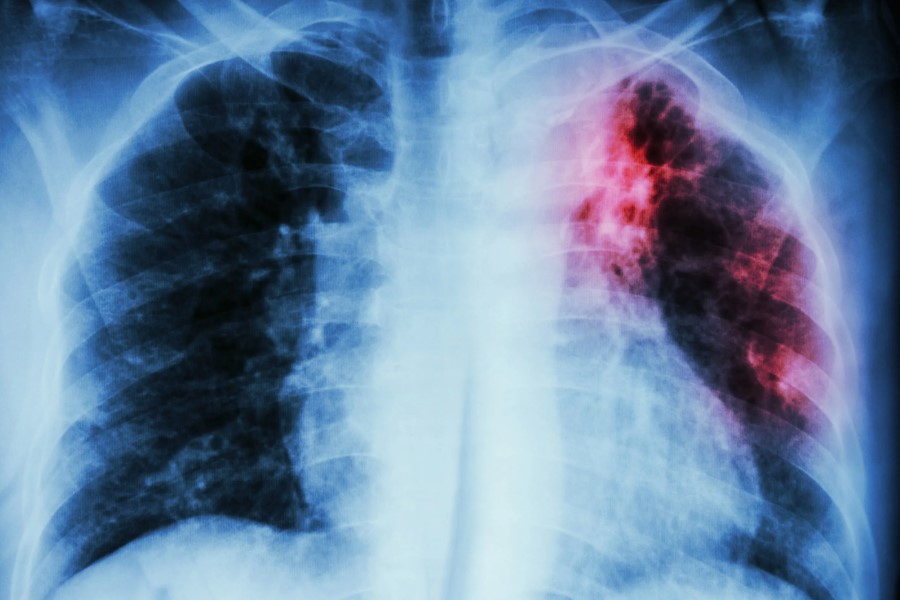

- Рентгенографія легень. Дає змогу побачити зміни у легенях, характерні для туберкульозу.